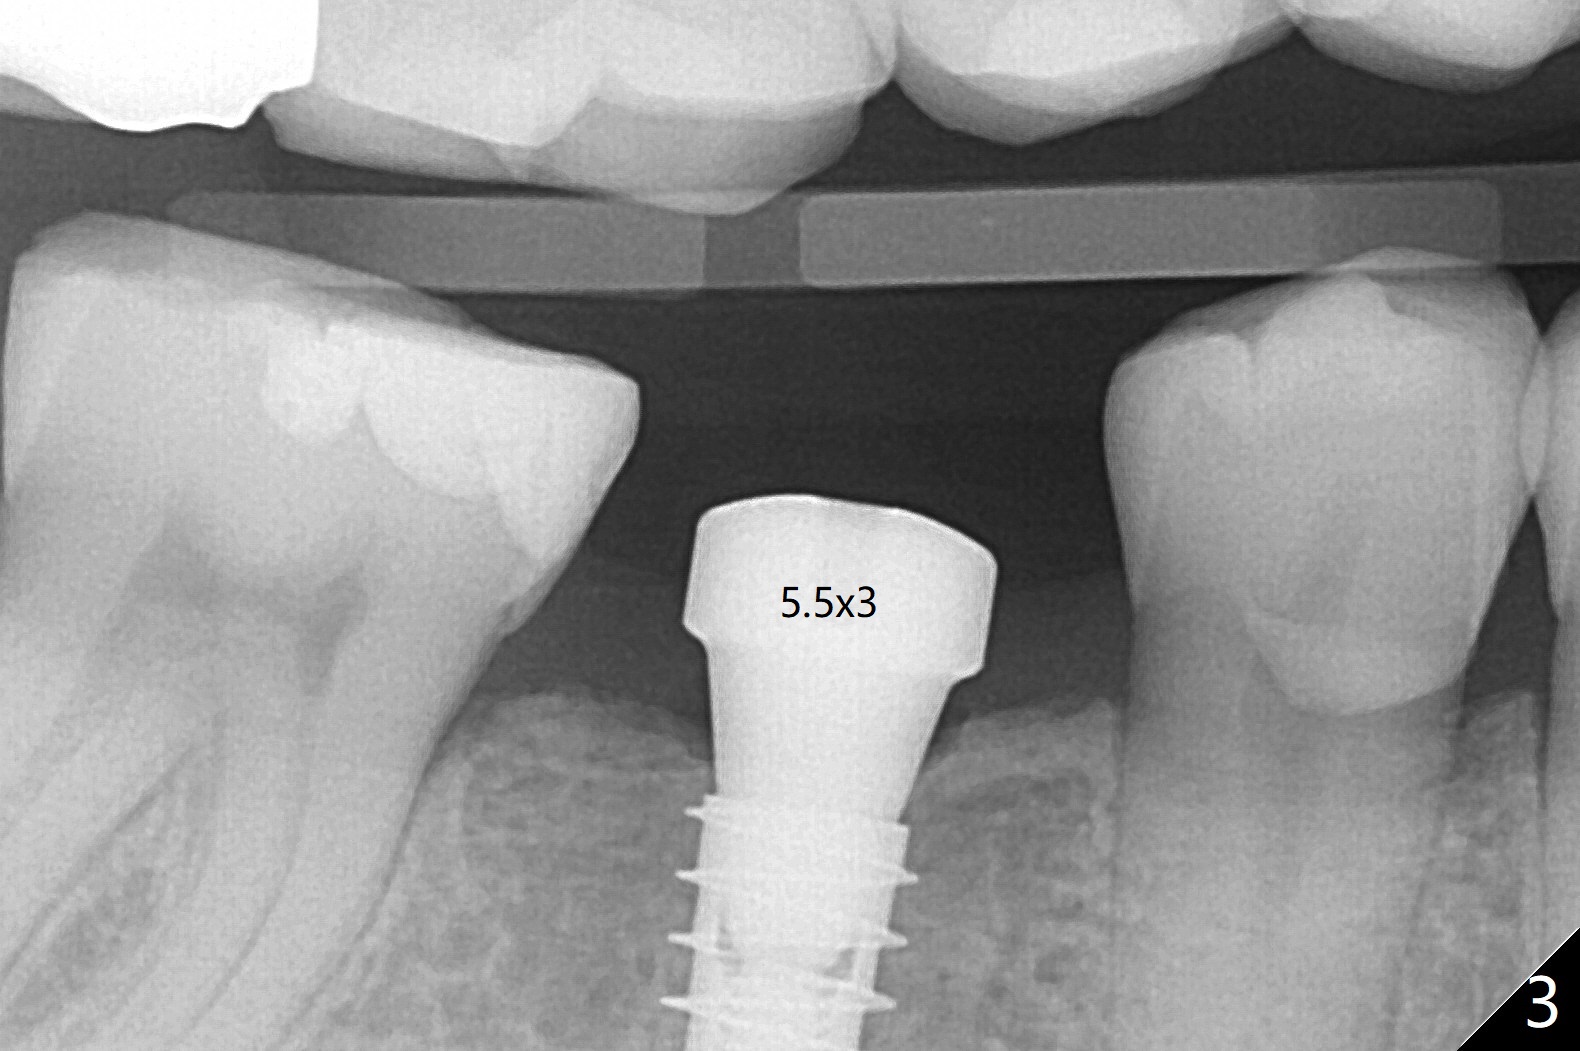

54岁男右下6缺失至少20年,牙槽嵴萎缩,使用导板顺利快速(五分钟)无痛植入4.5x11毫米植体(图一)。使用5.5毫米profile钻头后,放置6x2毫米愈合基台,后者明显没有就位(图二:箭头)。换一个基台,就位好些(图二)。再次使用同一个profile钻头后,可能去除一些近中皮质骨(图二:*),同一个基台完全就位(图三,四(红色虚线:下牙槽神经管上缘)),在愈合过程,基台不太可能脱落了。图一,二使用小sensor,而图三,四:大sensor。尽管使用小钻头(3.5毫米),扭力约20Ncm。